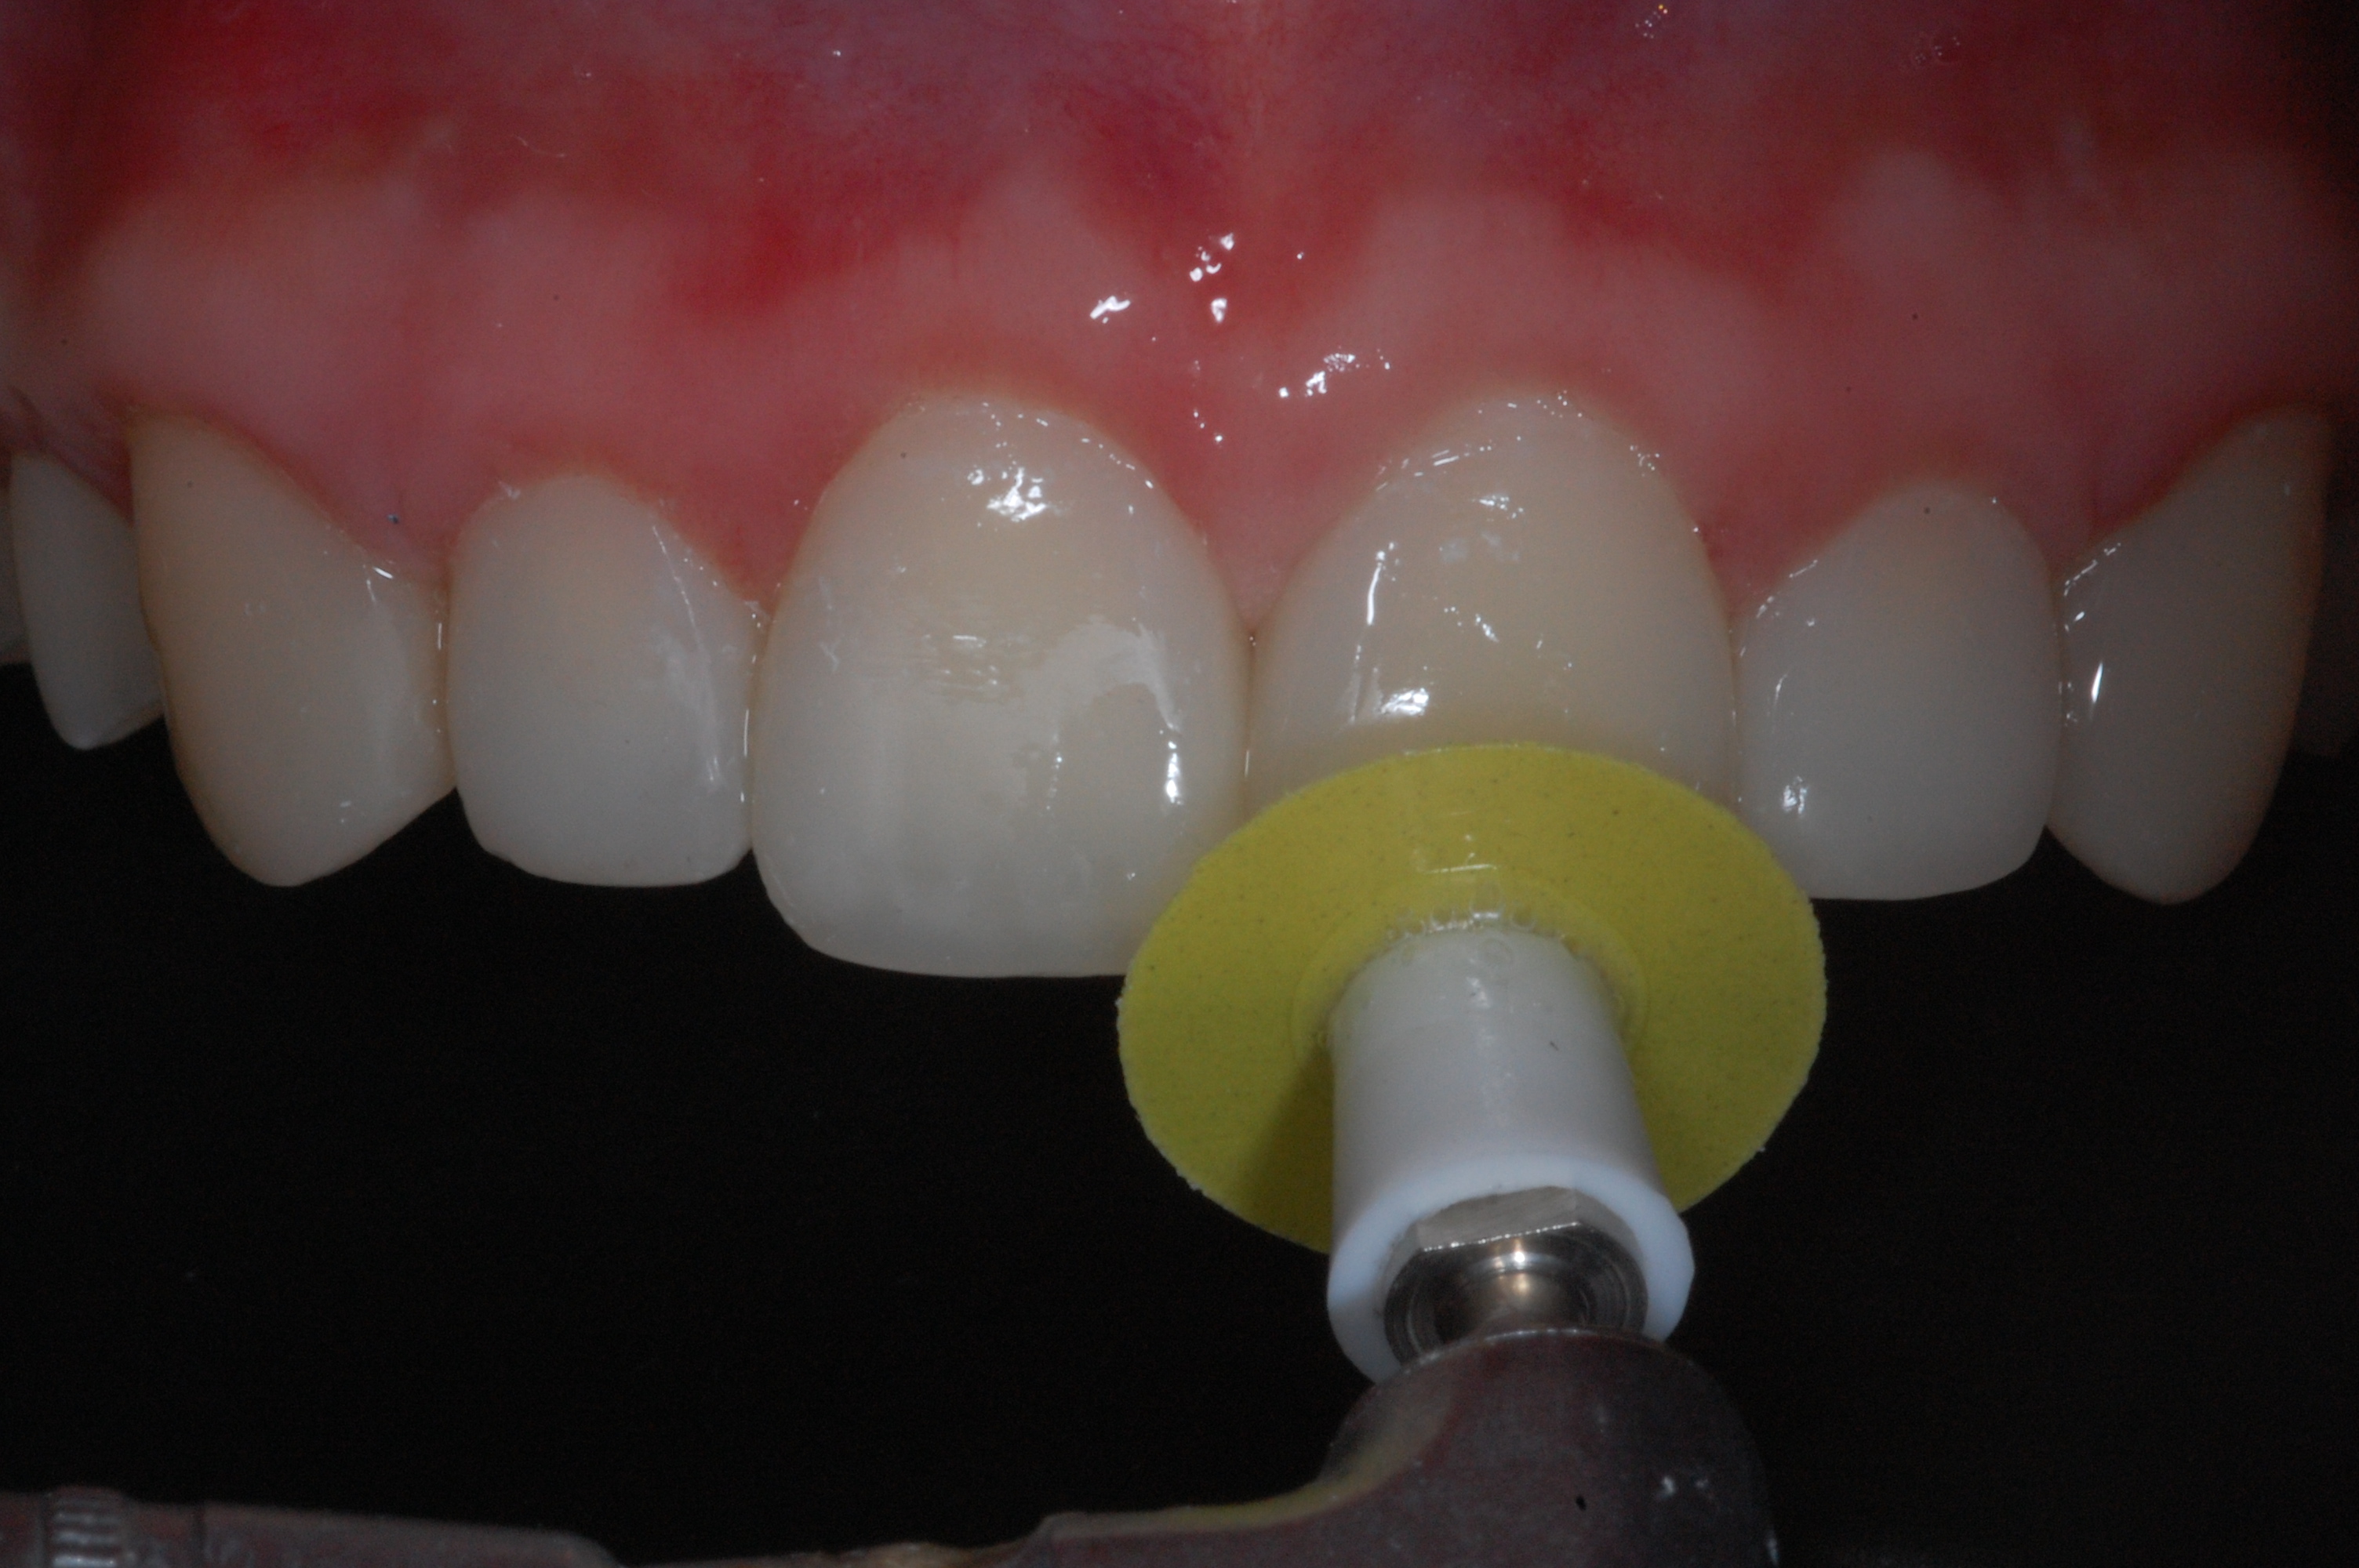

The presence of diastema, between anterior teeth, distorts a pleasing smile by concentrating the observer’s attention on the spaces. The patient’s needs and expectations must be considered in the process of treatment planning to ensure satisfaction with the treatment outcomes. There are many forms of therapy that can be used for diastema closure. A carefully developed diagnosis, which includes a determination of the causal elements and advanced treatment planning, allows the most appropriate treatment to be selected for each case. The aim of this paper is present a multidisciplinary approach as a solution to multiple diastemas in the anterior region using gingival tissue recontouring and direct adhesive restorations, with minimum wear of the dental structure, after the orthodontic intervention discussing the minimal intervention to obtain imperceptive and aesthetic final restoration. Thirty-six months after the treatment was carried out, the final aesthetic was maintained with all dental element details and gingival tissue harmony, without recurrence of periodontal pockets and the preservation of the tooth color and shape.